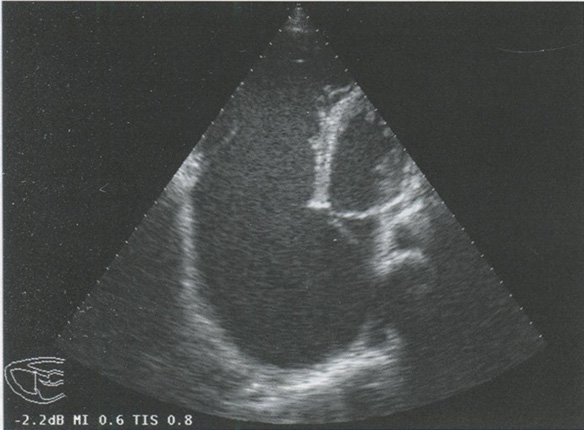

Оценка строения клапанов и подклапанных структур

При некоторых врожденных пороках сердца отмечаются особенности развития клапанов (расщепление створки клапана, врожденный стеноз клапана и т.д.). Крепление хорд клапанов также может быть не совсем обычным, например при аномалии Эбштейна или при полном атриовентрикулярном канале (рис. 2.4).

Рис. 2.4. Апикальная четырехкамерная позиция. Аномалия Эбштейна. Особенность крепления хорд трикуспидального клапана.